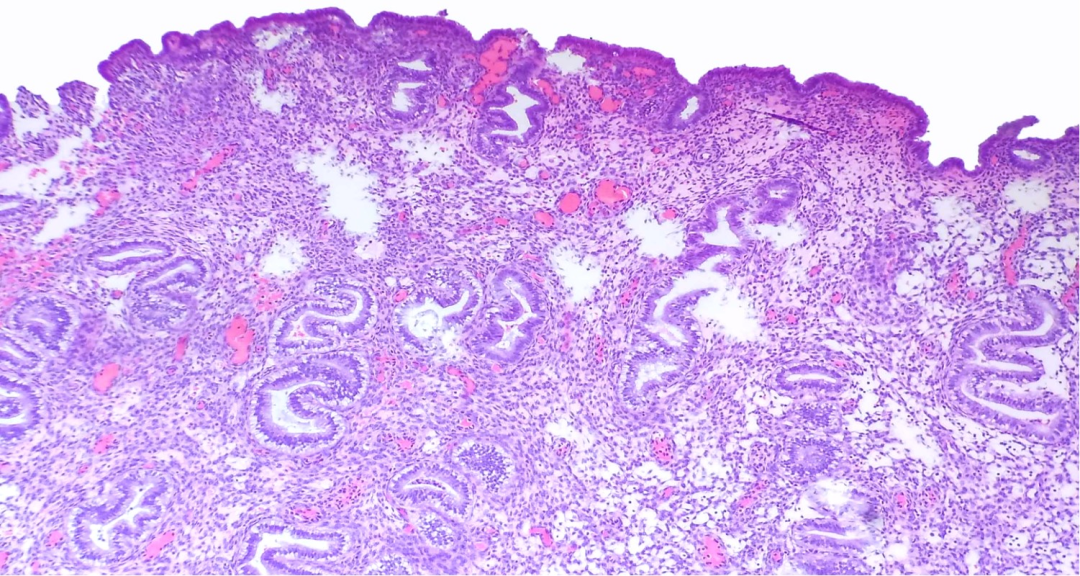

·增生期

非分支、非出芽、形状类似的腺体均匀地分布在整个间质中、间质细胞为单形性未分化细胞、胞浆稀少、细胞边界不清、血供来自发育均一的分枝状薄壁血管,典型者腺体-间质比例为1:1。增生早期,腺体呈管状,管腔狭窄,当增生继续时,腺体盘绕逐渐增加,腺腔增大。

进一步发展的标志是:假复层、核分裂活跃、细长的伴有致密染色质的上皮细胞以及核分裂活跃的间质细胞。血管不明显,类似于毛细血管